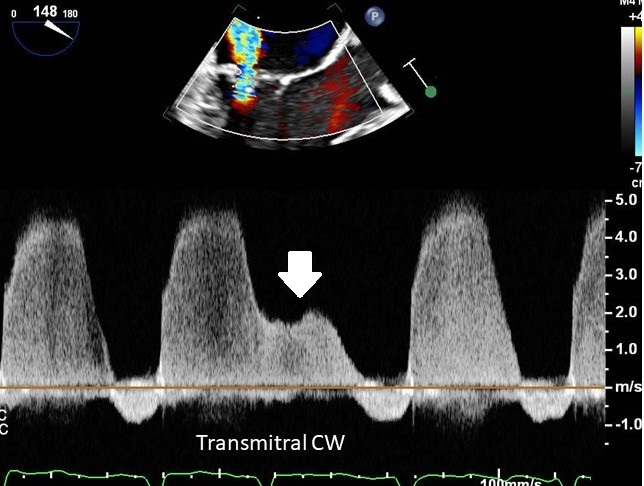

Recognize the cute device bouncing in the LAA? Two years after transcatheter mitral paravalvular leak closure — Amplatzer device found embolized to the left atrial appendage. A reminder: closure success is more than the immediate result #CardioTwitter #StructuralHeart PCRonline 🫀